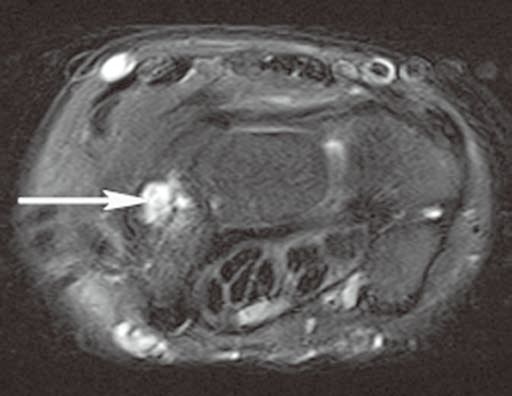

图2腕管腱鞘囊肿

A

B

C

横轴位(A)和冠状位(B)脂肪抑制T2WI示腕管内较大的腱鞘囊肿,内含液体而呈高信号。冠状位脂肪抑制增强T1WI(C)示囊壁强化而囊液不强化